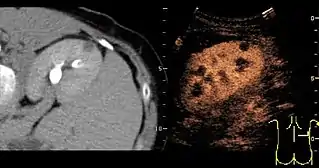

Unspecific cortical lesion on CT scan is confirmed cystic and benign with contrast-enhanced renal ultrasonography.

A CT scan is the first choice modality for workup of solid masses in the kidneys. Nevertheless, hemorrhagic cysts can resemble renal cell carcinomas on CT, but they are easily distinguished with Doppler ultrasonography (Doppler US). In renal cell carcinomas, Doppler US often shows vessels with high velocities caused by neovascularization and arteriovenous shunting. Some renal cell carcinomas are hypovascular and not distinguishable with Doppler US. Therefore, renal tumors without a Doppler signal, which are not obvious simple cysts on US and CT, should be further investigated with contrast-enhanced ultrasound, as this is more sensitive than both Doppler US and CT for the detection of hypovascular tumors.[3]